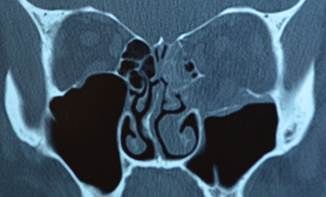

Fractura orbitaria

Las fracturas orbitarias se pueden encontrar aisladas o asociadas a otras fracturas faciales

Cuando afectan solamente las paredes, respetando el reborde orbitario se denominan fracturas puras

Se han propuesto 2 teorías (para tipo blowout): conducción ósea e hidráulica

Los signos clínicos más frecuentes para una fractura de piso tipo blow out en adultos son: equimosis periorbitaria y hemorragia subconjuntival.

5% de los adultos con traumatismo craneoencefálico tienen fracturas orbitarias, y la mitad de ellas requerirán intervención quirúrgica.

Su resolución depende de los síntomas asociados y el tamanio de la misma. Los tratamientos pueden ir desde observación hasta reconstrucción de la fractura con distintos materiales.

Las indicaciones quirúrgicas más comúnmente utilizadas son:

• Diplopía en ortoposición

• restricción a la supra o infraducción dentro de los 30 grados de la visión primaria.

• Confirmación radiológica de fractura mayor del 50% de la pared afectada.

• Enoftalmos mayor a 2mm o cosméticamente inaceptable para el paciente.